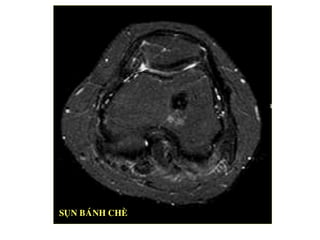

SUÏN BAÙNH CHEØ

ACL PCL

- Pd :TR daøi, TE ngaén xem suïn cheâm, suïn

khôùp, suïn baùnh cheø

- Med 3d xem suïn